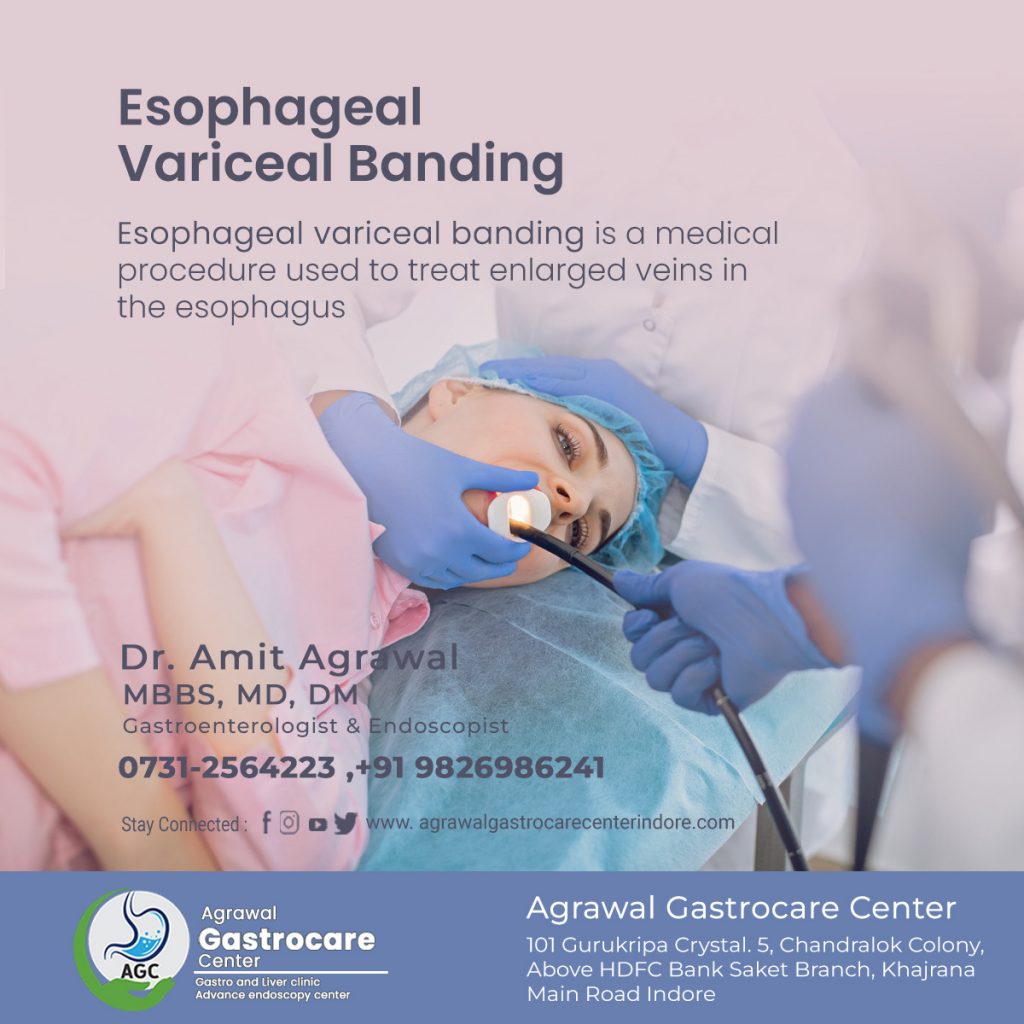

Esophageal Variceal Banding Procedure Risk Need Agrawal Gastrocare